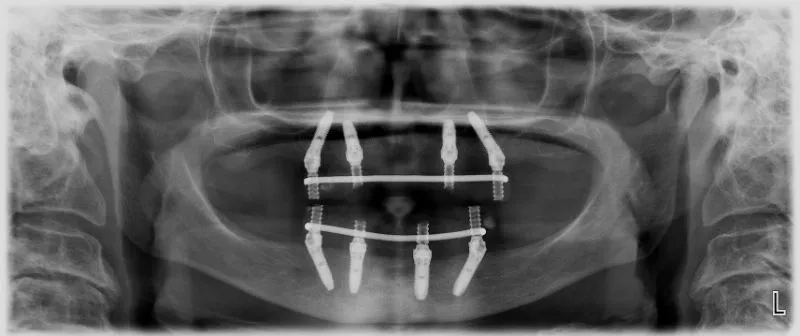

All-On-4™ e иновативна рехабилитационна концепция за лечение, позволяваща в едно посещение с помощта на специални зъбни импланти, без добавяне на костни заместители, изцяло обеззъбени пациенти да получат неподвижни зъби, които изглеждат и функционират като естествени.

- Поставят се четири импланта в костта.

- Към тях се свързват специални мулти-юнит абатмънти.

- Към мулти юнит абатмънтите се свързва конструкцията.

- рехабилитация на тотално обеззъбена горна или долна челюст /или такива, на които предстоят да се извадят и последните зъби /с четири зъбни импланта, поставени във всяка челюст/,

- елиминира се нуждата от костни заместители,

- намален брой хирургични процедури,

- поставяне на временна, винтово закрепена, несваляща се конструкция в деня на хирургията,